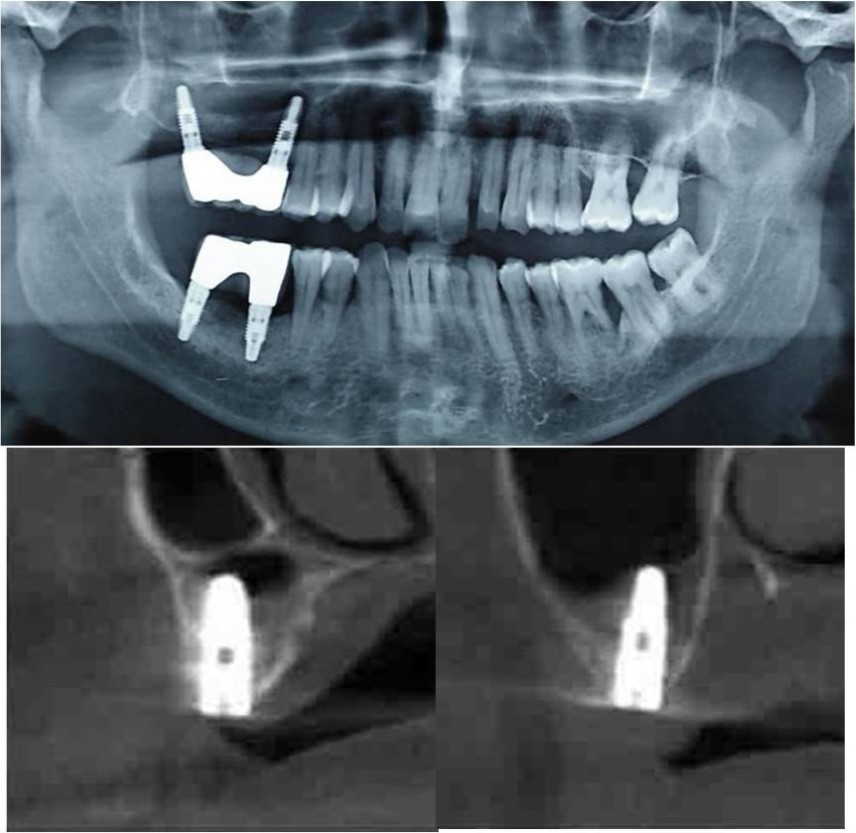

Figure 9.(a,b) Pre-treatment OPG and cross section of CBCT showing residual alveolar bone height for Case No.2

Figure 10.(a,b) Post-treatment OPG and cross section of CBCT showing residual alveolar bone height for Case No.2